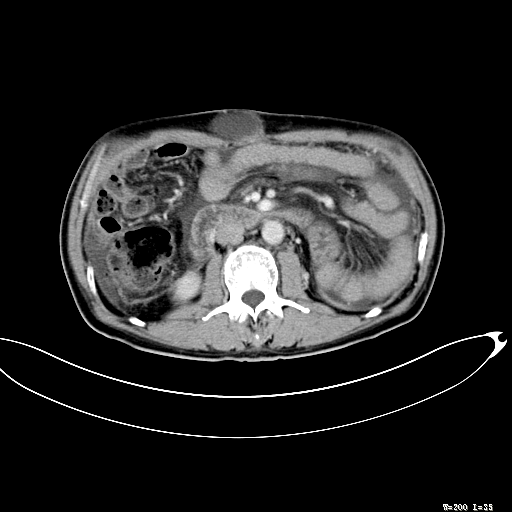

标题: CT27080:腹壁肿物?

男,52岁,门脉高压断流术后1年,发现腹部肿物2月。

1)前腹壁中线区(脐上方)囊性占位性病变,考虑淋巴囊肿。2)腹水。